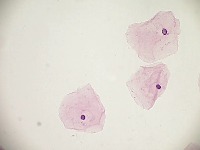

Cervical Cancer Screenings: The "PapDetector" can be used for the initial screening in detecting cervical cancer. Its ability to classify different cellular structures could provide invaluable assistance in large-scale cervical cancer screening tests, making the entire process more efficient.

Medical Research: Scientists and researchers can use this model to identify and further study these cellular structures. This could improve the understanding of various conditions related to cell abnormalities, thus leading to new treatments or diagnostic methods.

Training Medical Students: The "PapDetector" can also serve as a learning tool for medical students, enabling them to visually learn and identify cell structures that denote normal and abnormal cases.

Pharmaceutical Development: The computer vision model could be utilized in the pharmaceutical industry to screen the effects of drug treatments on cell morphology – highlighting normal, HSIL, LSIL, ANORMAL, Koilocytes changes in response to pharmaceutical compounds. This information would be useful in drug development and efficacy trials.